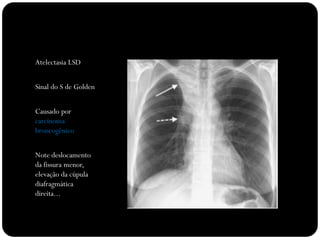

O que está anormal?

Atelectasia LSD

Sinal do S de Golden

Causado por

carcinoma

broncogênico

Note deslocamento

da fissura menor,

elevação da cúpula

diafragmática

direita...